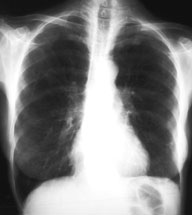

Eine 70-jährige Patientin meldet sich bei Ihnen in der Praxis mit Verschlechterung des Allgemeinzustandes seit 4-5 Wochen und Fieber bis maximal 38.5 Grad.

Des weitern klagt sie über einen trockenen Husten. Ausser einer arteriellen Hypertonie besteht als Vorerkrankung eine leichte COPD. Da Sie ausser dem Husten keinen klinischen Fokus für einen Infekt finden, entschliessen Sie sich für ein Thorax-Bild. Optimalerweise haben Sie sogar noch ein pa-Thorax von vor 2 Jahren zum Vergleich:

Welche Differentialdiagnosen kommen in Frage (mehrere richtige Antworten möglich)?